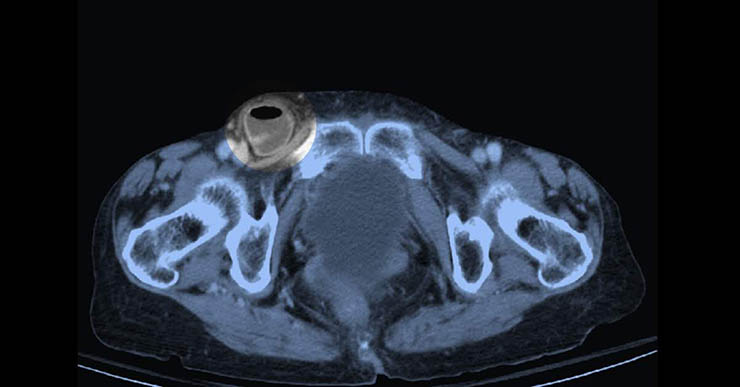

| 右側鼠蹊部嵌頓型疝氣,可看見小腸卡住 |

經檢視診斷為鼠蹊部嵌頓型疝氣,造成腸子卡住,於是安排緊急手術處理,所幸手術順利,腸子還沒有壞死,患者術後觀察一、二天後順利出院。

答:要。鼠蹊部疝氣分兩種:腹股溝疝氣及股疝氣。不管男女,腹股溝疝氣都是比較常見的,但女性有明顯較多的股疝氣。股疝氣最值得注意的是它很容易造成腸子的嵌頓、壞死。有較高的機率要做到腸段的切除。